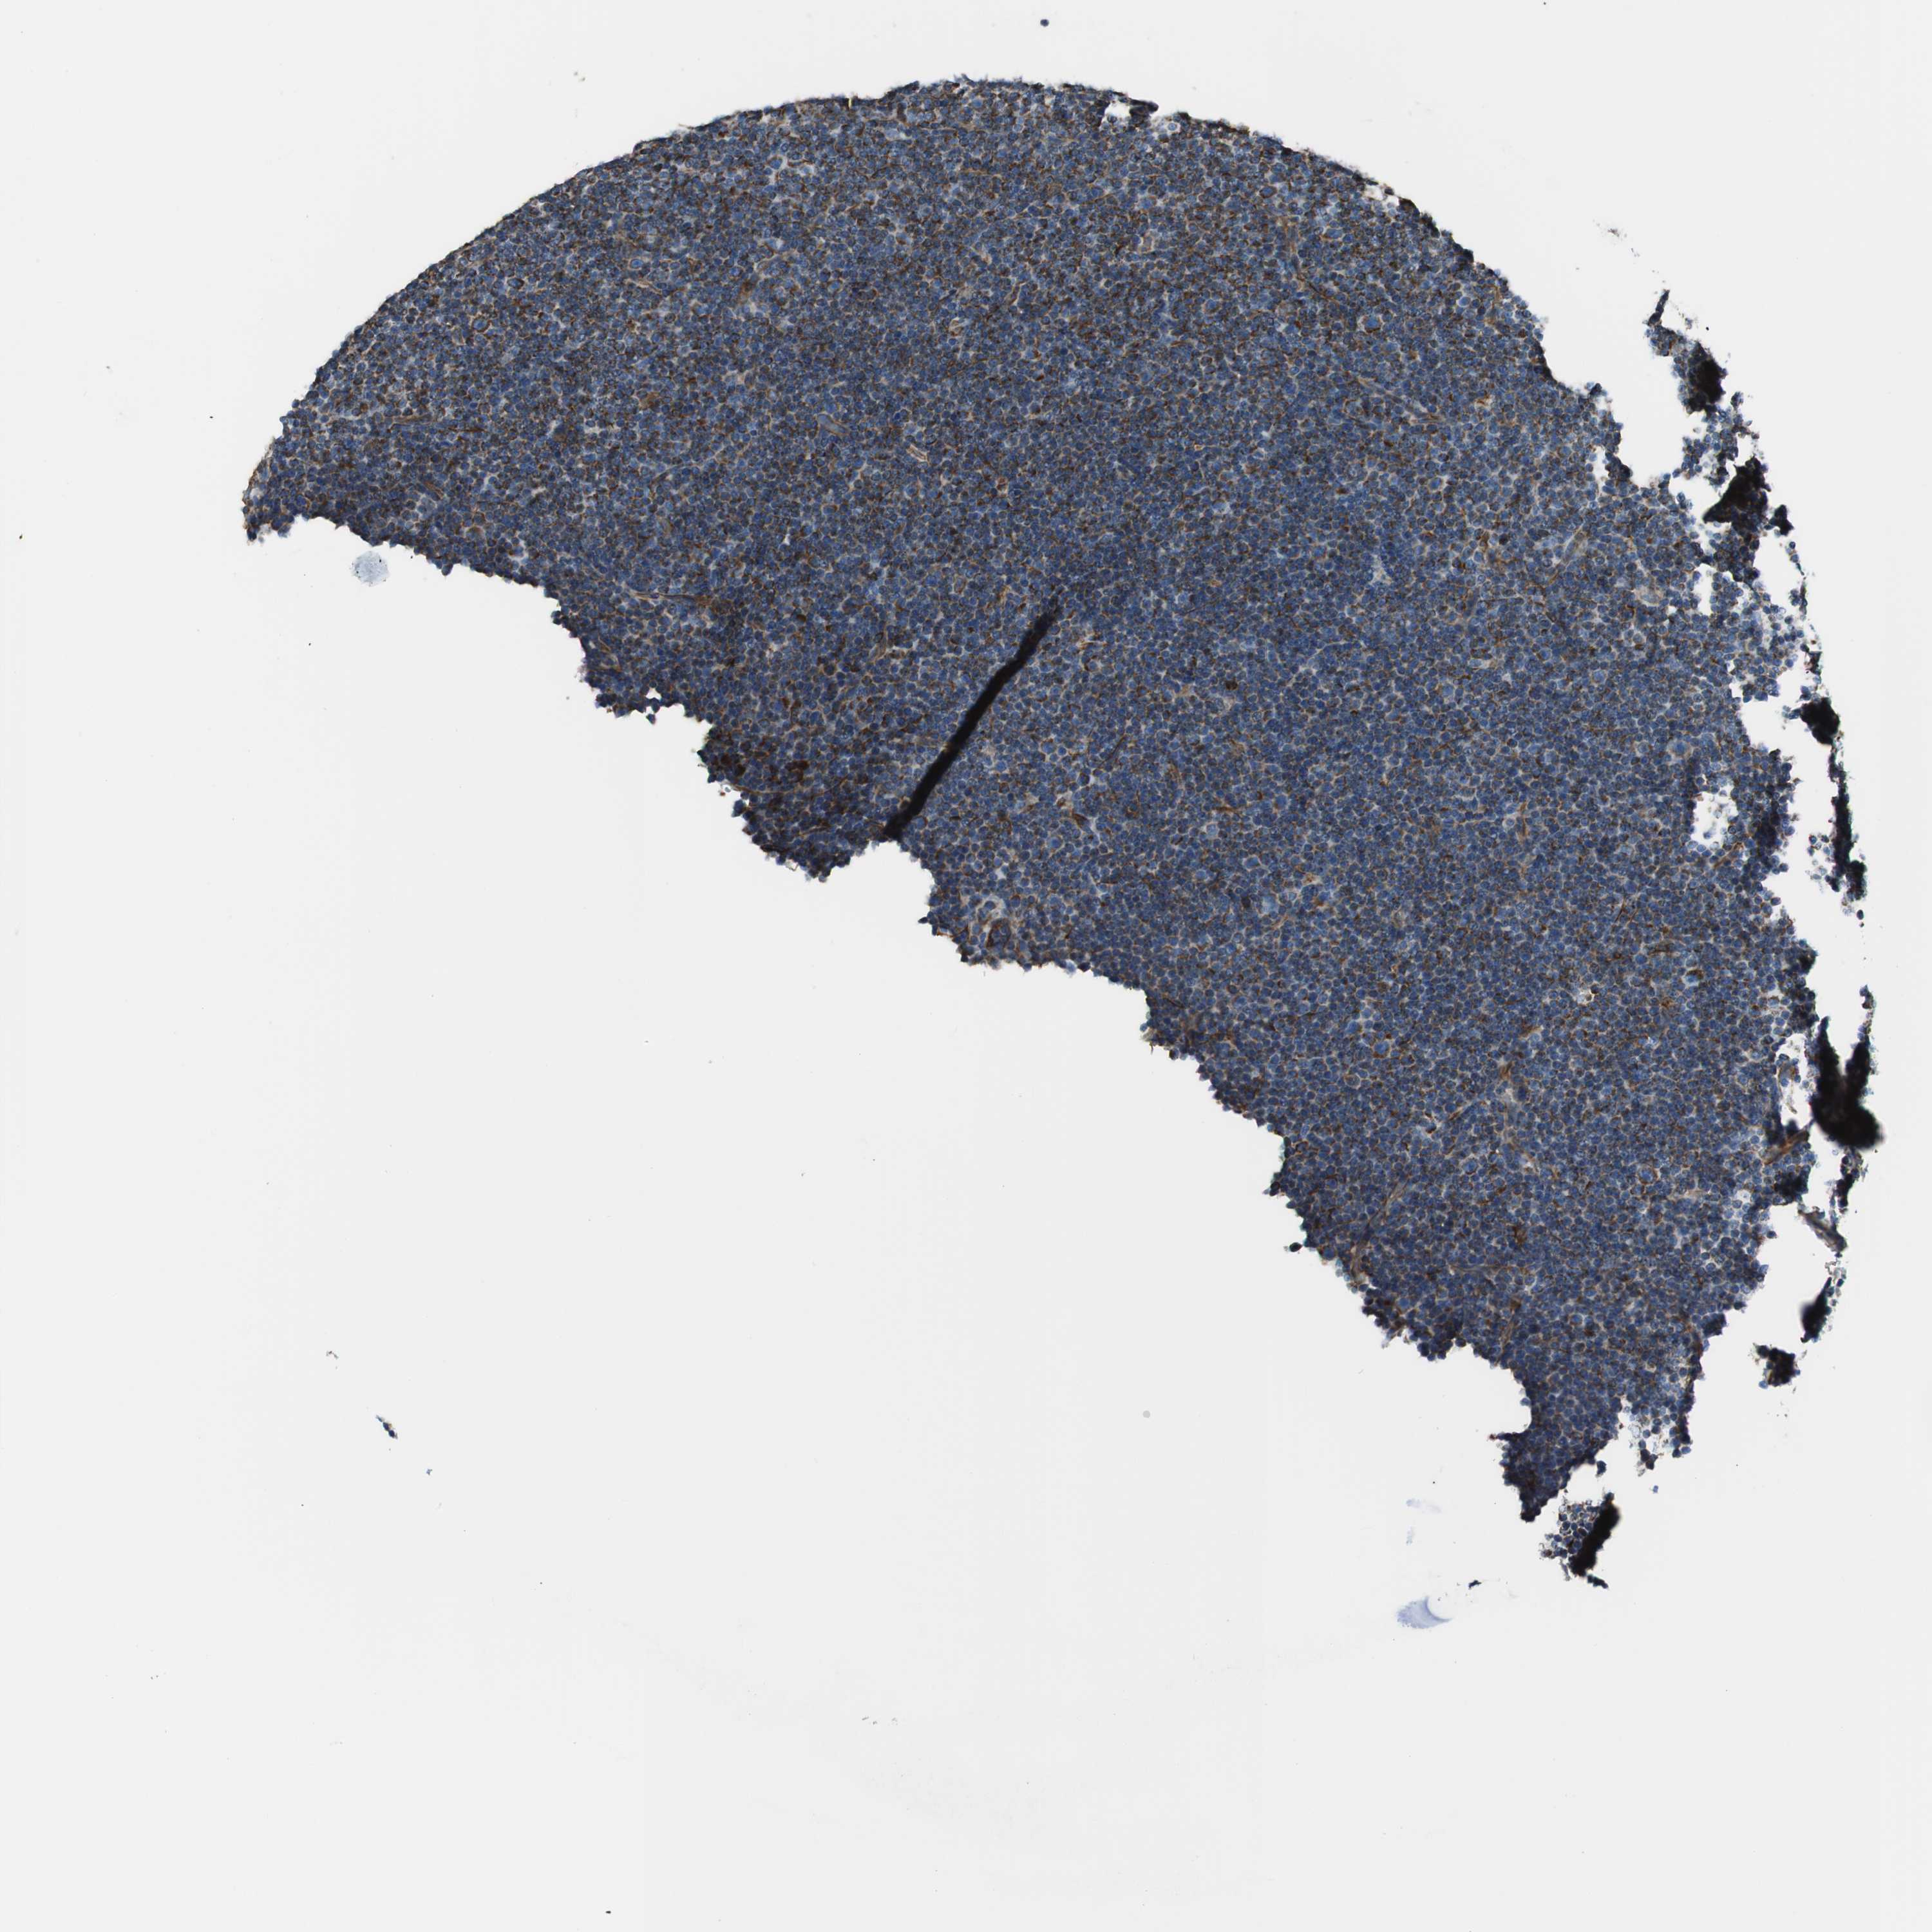

CANCER LYMPHOMA Show tissue menu

LYMPHOMA - Protein expressioni

A mouse-over function shows sample information and annotation data. Click on an image to view it in a full screen mode. Samples can be filtered based on level of antibody staining by selecting one or several of the following categories: high, medium, low and not detected. The assay and annotation is described here.

Each image is clickable and will lead to virtual microscopy that enables deeper exploration of all samples and also displays staining intensity scores, fraction scores and subcellular localization as well as patient and tissue information for each sample.

Antibody HPA009701

Hodgkin's disease, NOS

Malignant lymphoma, non-Hodgkin's type, Low grade

Malignant lymphoma, non-Hodgkin's type, High grade